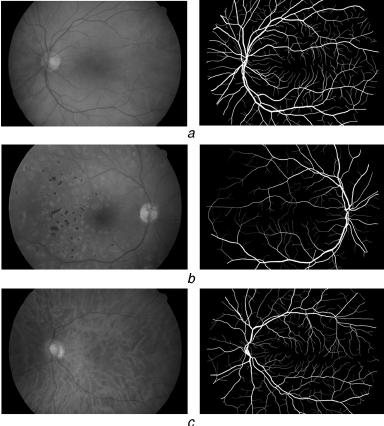

HRF تعني High-Resolution Fundus (قاع العين عالي الدقة)، وهي مجموعة بيانات لتجزئة الأوعية الدموية في شبكية العين. تم إنشاء مجموعة البيانات هذه بواسطة مجموعة بحثية تعاونية لدعم الدراسات المقارنة لخوارزميات التجزئة التلقائية لصور قاع الشبكية.

تتضمن مجموعة البيانات ما يلي:

- 45 صورة

- 15 مجموعة فرعية (تحتوي كل مجموعة فرعية على صورة واحدة لقاع العين السليم، وصورة واحدة لمريض اعتلال الشبكية السكري، وصورة واحدة للجلوكوما)